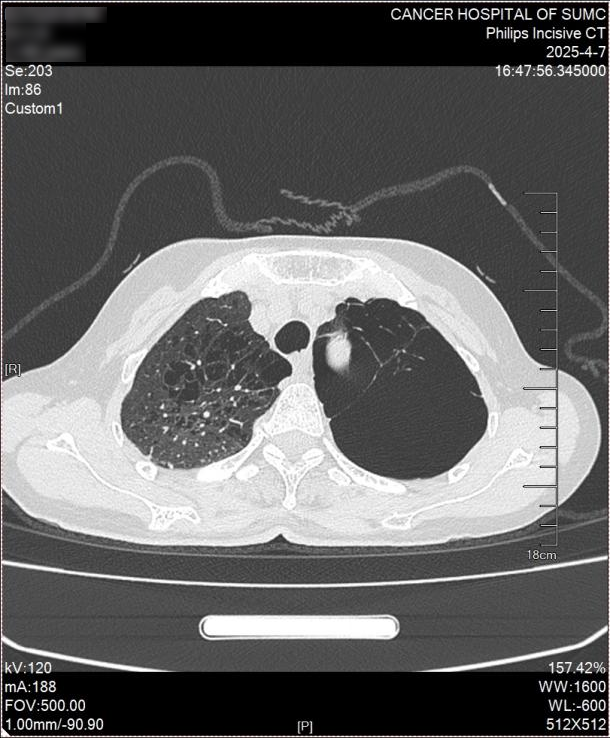

图片 1.png

患者双肺严重肺气肿,左侧胸腔几乎全部被巨大肺大泡占据